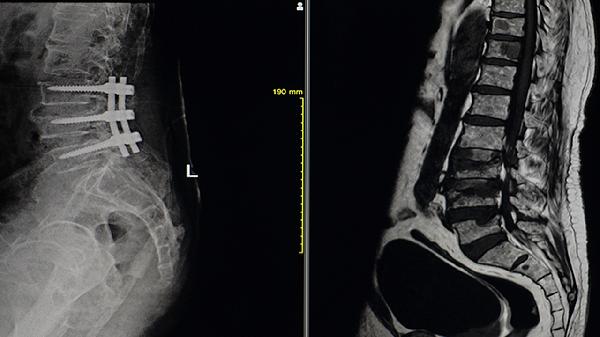

当疾病进展至中晚期出现脊柱畸形或髋关节强直时,需骨科介入评估手术指征。骨科医生可通过X线、CT等检查判断关节破坏程度,必要时行人工髋关节置换术或脊柱矫形手术。对于急性疼痛发作或活动受限的患者,骨科可提供物理治疗和康复指导。